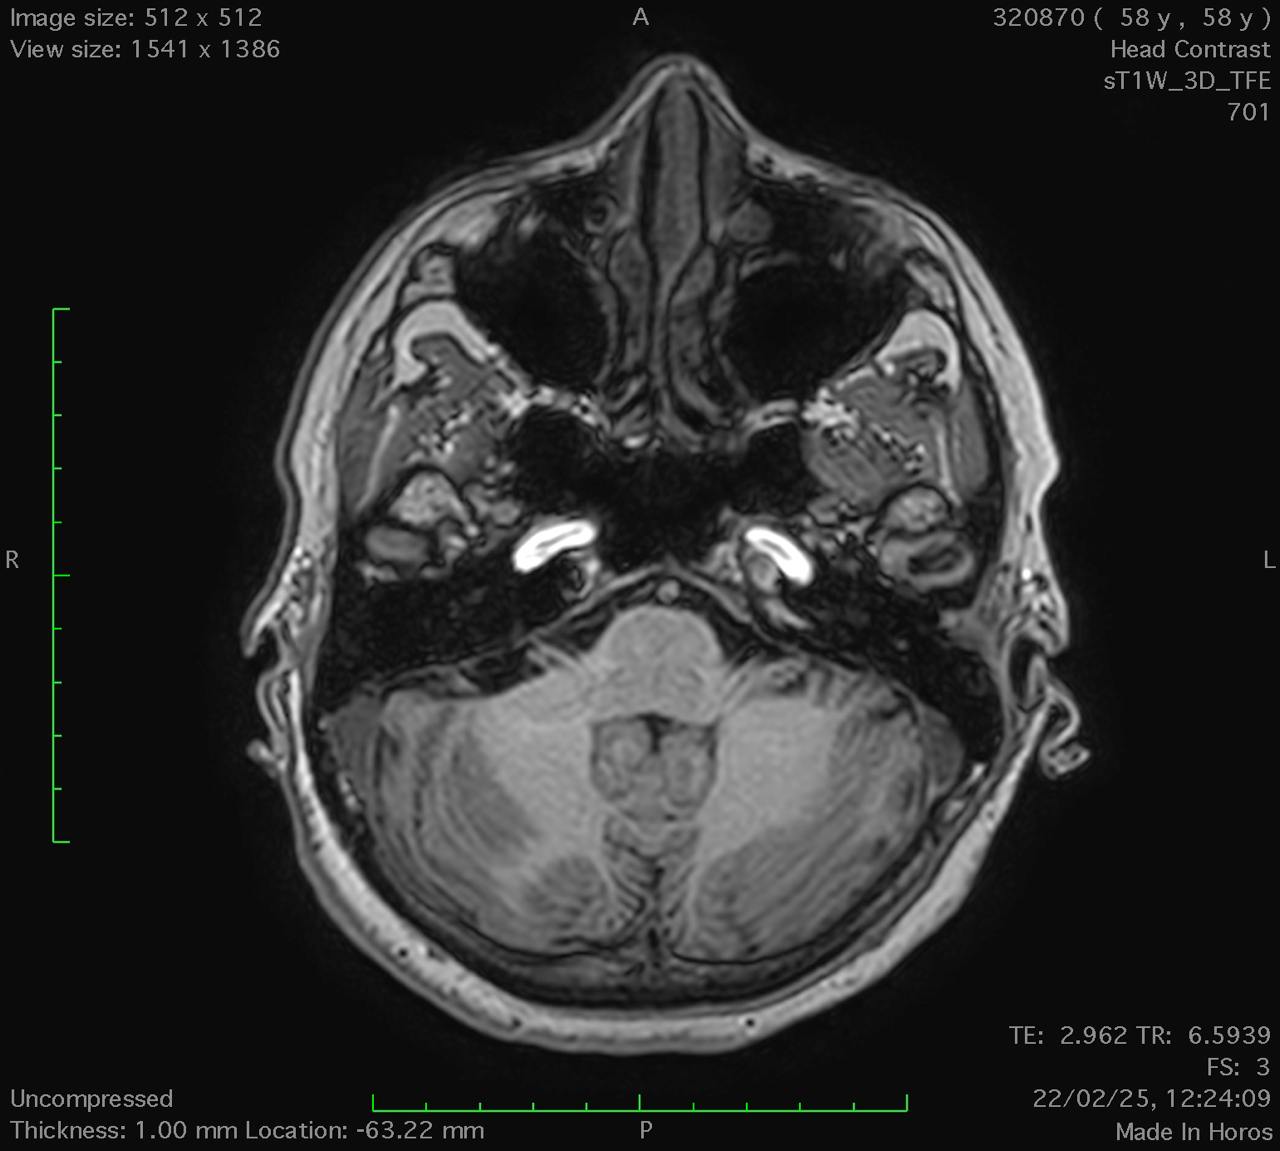

Results: Cerebellar ataxia, bilateral lower limb sensory loss, absent deep tendon reflexes, and marked bidirectional nystagmus were all found during the neurological test. Bilateral vestibular areflexia was established by video head impulse testing (vHIT). Electroneurography demonstrated sensory neuronopathy, and brain MRI showed mild cerebellar atrophy, particularly in the vermis, without evidence of central demyelination or structural abnormalities suggestive of other neurodegenerative conditions. The diagnosis of CANVAS was highly supported by the combination of clinical, electrophysiological, and imaging evidence, even if genetic confirmation was not feasible due to financial constraints CANVAS.

Conclusion: Suspicion of CANVAS should be raised in the presence of bilateral vestibular impairment, sensory neuropathy, progressive ataxia, and severe bidirectional nystagmus. The diagnosis is further supported by moderate cerebellar atrophy seen on MRI. When genetic testing is not available, a diagnosis can nevertheless be made using clinical and paraclinical findings, even though genetic testing is the gold standard for confirmation. Patient care can be enhanced, and needless treatments can be avoided, by recognizing CANVAS.

Axial T1-weighted MRI.